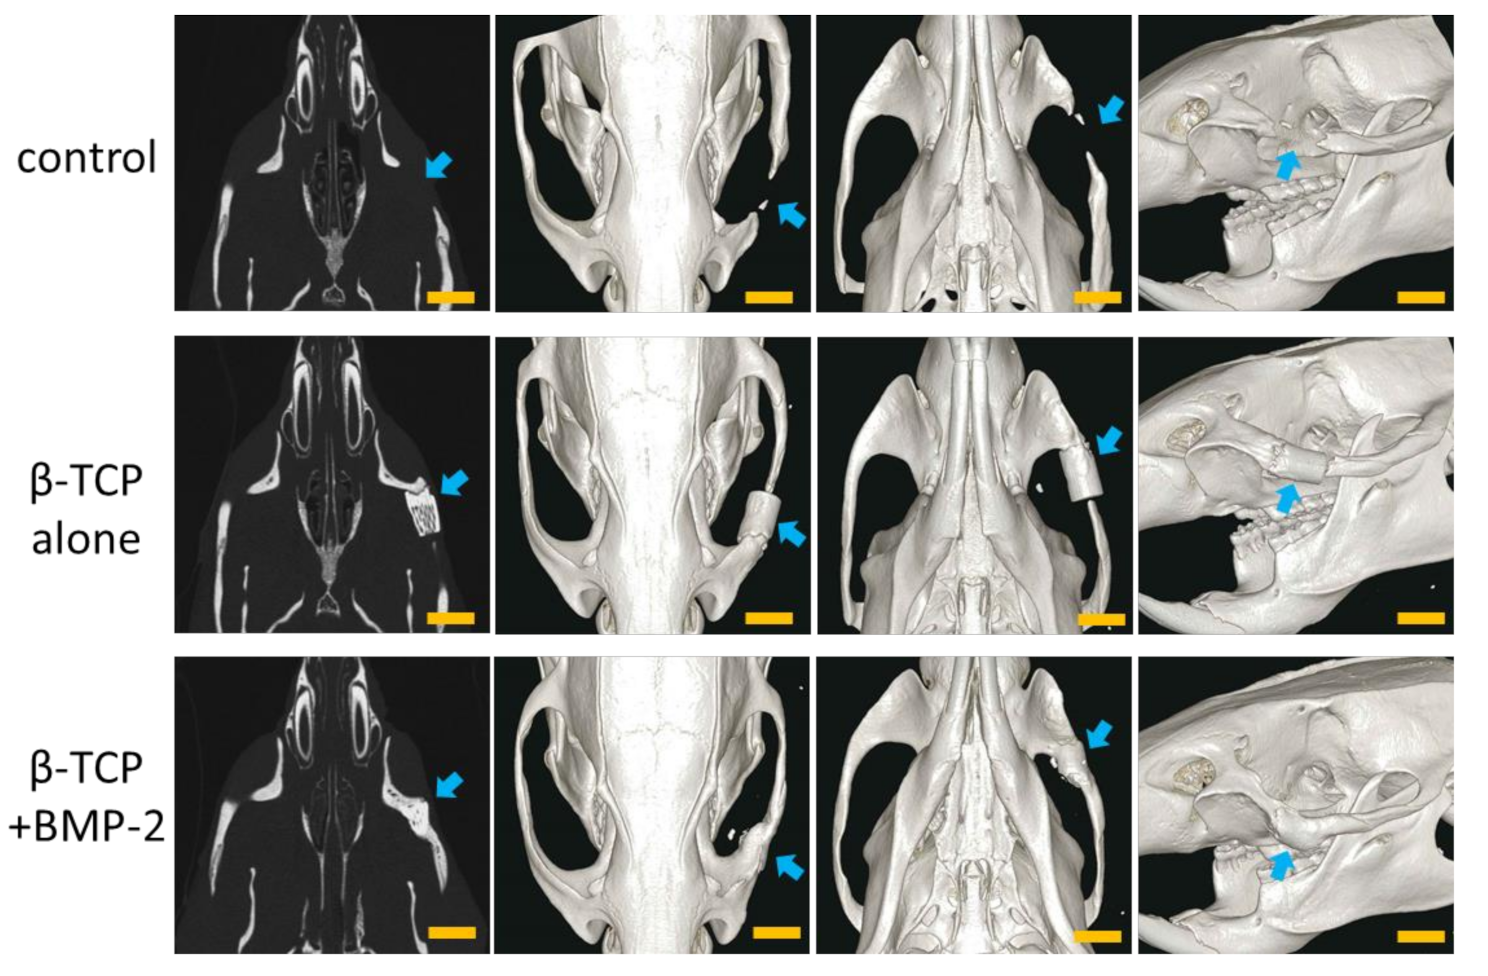

In the control group, slight bone regeneration was observed from the excised margin. However, bone defects remained even 6 months after implantation, and continuous zygomatic arch regeneration was not observed (Figure 3, top).

In the TCP group, fusion with the zygomatic bone was observed at the anterior site 6 months after implantation, but there was no union at the posterior site. A slight gap also remained between β-TCP and the osteotomy stump. In addition, β-TCP was hardly absorbed, and the shape of the material was maintained (Figure 3, center).

In the BMP group, complete union with the zygomatic bone was observed 6 months after implantation. In addition, the β-TCP was partially absorbed and had a similar morphology to that of the zygomatic bone on the unaffected side (Figure 3, bottom).

Figure 3. Micro-computed tomography (CT) images of the heads of rats at 6 months after the operation using Matrigel. Top: control group; center: β -tricalcium phosphate (TCP) alone group (TCP group); bottom: β -TCP + BMP-2 group (BMP group). The arrows indicate the surgical sites. Scale bars = 5 mm.